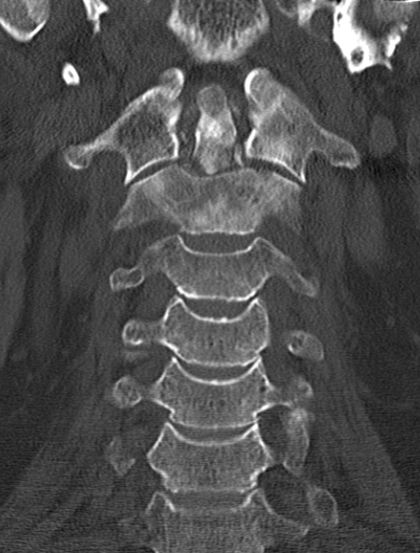

75-jähriger Mann, der wegen unklarer Schmerzen im

Nackenbereich abgeklärt wurde. Als Ursache der Knochenmetastasen wurde ein lokal

fortgeschrittenes Prostatakarzinom (PSA 143, Gleason 7) gefunden.![]() |

Das T2-Bild im MRT der HWS zeigt eine

Signalverstärkung im 7.HWK. Der Densbereich ist stark umgebaut.![]() | |||||||||||||||||||